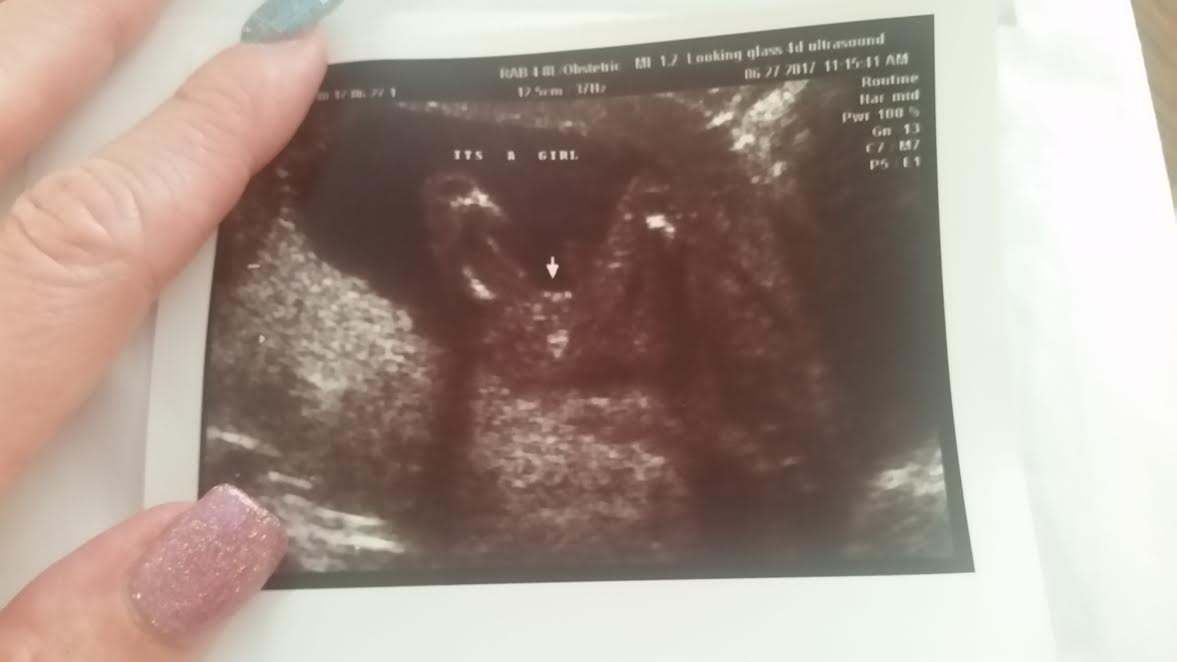

Okay we were told last week that we are having a baby girl! As a boy mom I can remember my son sticking wayyyyyy out there! However, I'm not sure what girl parts are supposed to look like. I was told the three little lumps are labia and clitoris, do you agree? We are so excited!

Re: Girl Confirmation